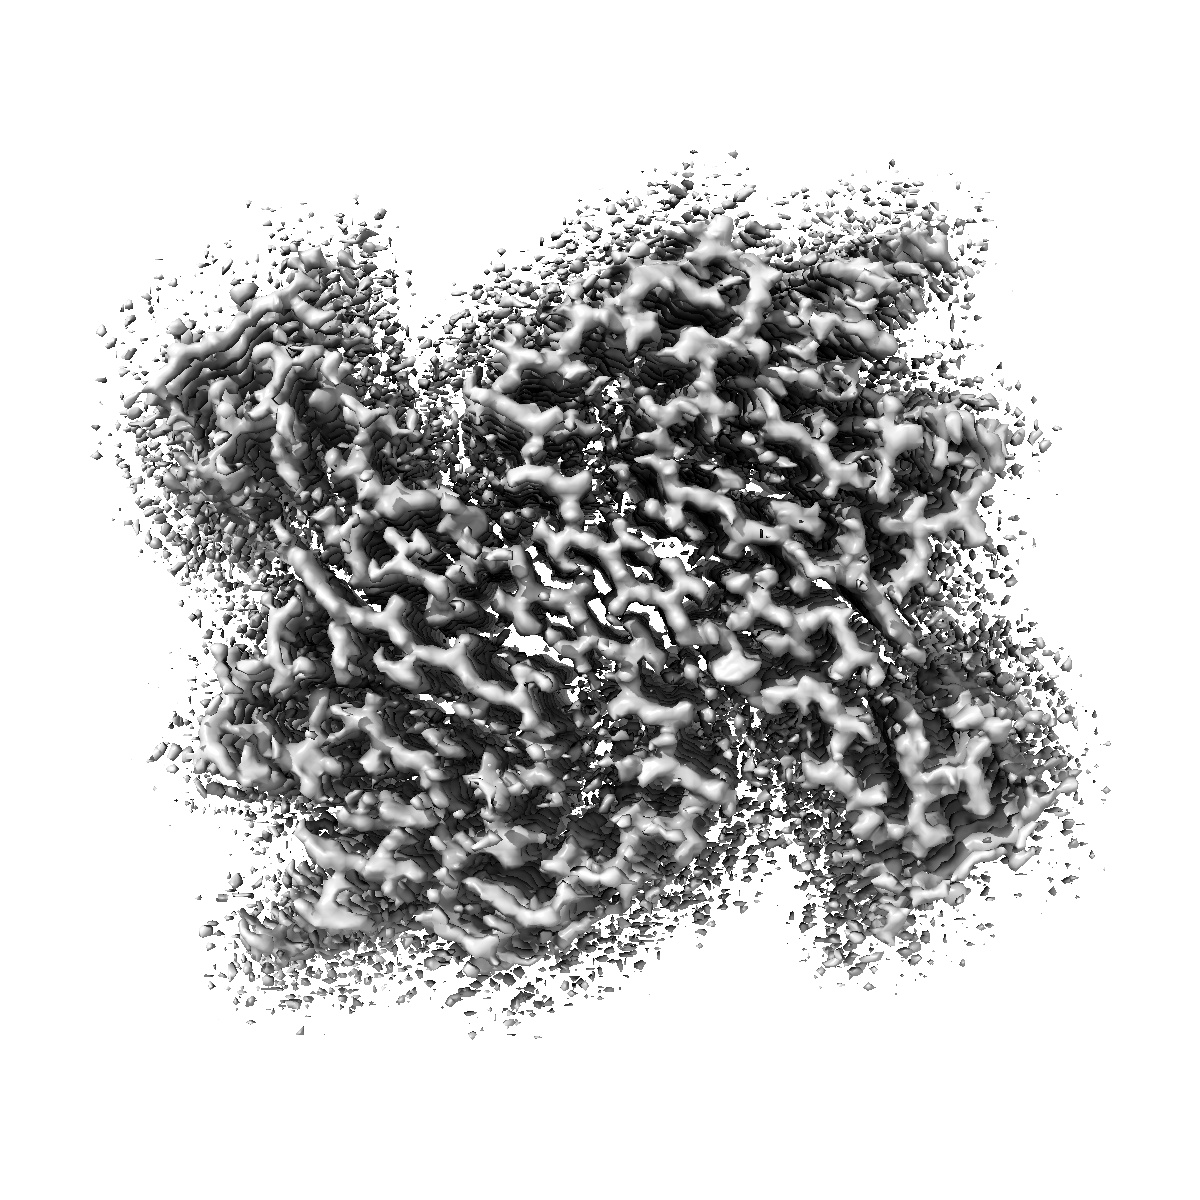

Structure of recombinant alpha-synuclein fibrils 1B capable of seeding GCIs in vivo

Helical reconstruction1.93 Å

Sample: recombinant alpha-synuclein fibril

Synthetic alpha-synuclein fibrils replicate in mice causing MSA-like pathology.

(2025) Nature , 648 , 409 - 417